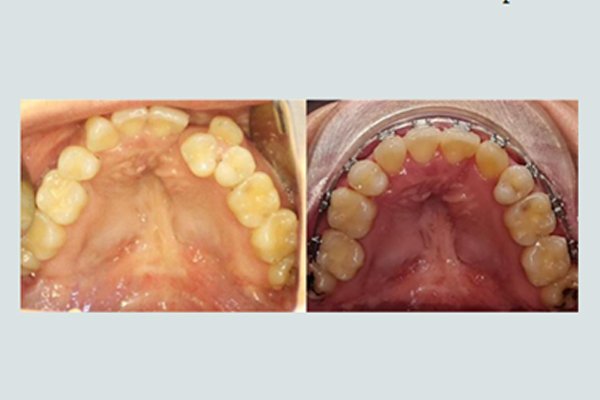

Dental Problems like, lack of , misplaced or extra teeth.

Ideal treatment is 3-6 months for cleft lip patients and 9-18 months for cleft palate Patients.

Surgical treatment called palatoplasty and Cheiloplasty are carried out on babies from the age of 3 month to 12 months [ Uk ], 6-14 month [ USA ], EU 3-17 Months and India 3-18 Months.